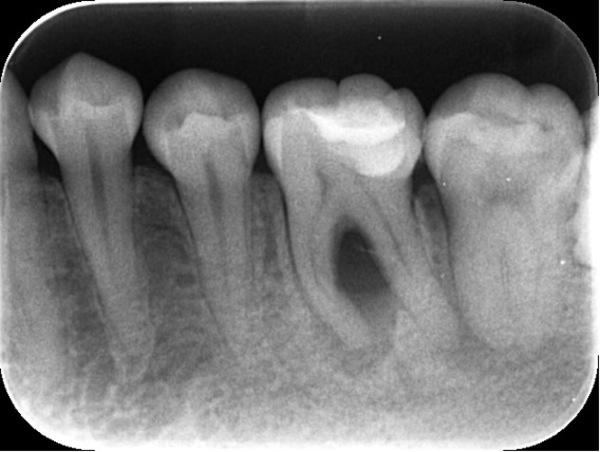

マイクロスコープ下で昔の詰め物を除去していきます。

う蝕(むし歯)検知液を用いるとX線では断定しきれなかった、新たなむし歯が確認できます。

むし歯を取り切り、神経(歯髄)の存在している髄腔まで到達しました。

神経が生きている歯だと出血がありますが、今回は術前の診断通り、既に神経が死んでいるため出血がありません。中からは独特の腐敗臭がします。

(※出血が絶対に起こらない訳ではありません)